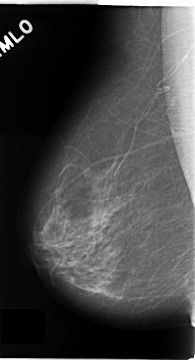

C_0135_1.RIGHT_MLO

RIGHT_MLO LINES 4672 PIXELS_PER_LINE 2528 BITS_PER_PIXEL 12 RESOLUTION 50 NON_OVERLAY